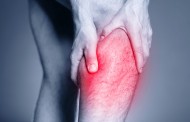

Wer häufig unter Wadenkrämpfen leidet, weiß, wie unangenehm und schmerzvoll diese sein können. Besonders tückisch: Krämpfe in den Waden kommen meist ohne jede Vorwarnung und besonders gern i... Read more